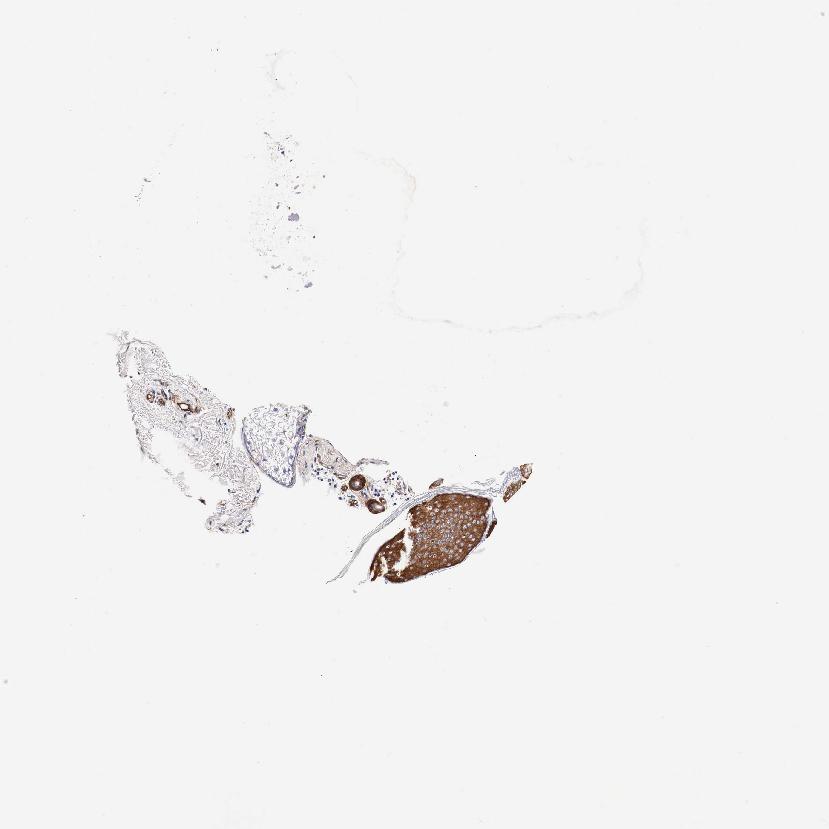

SKIN 1 - Antibody stainingi

Antibody staining in the annotated cell types in the current human tissue is reported as not detected, low, medium, or high, based on conventional immunohistochemistry profiling in selected tissues. This score is based on the combination of the staining intensity and fraction of stained cells.

Each image is clickable and will lead to virtual microscopy that enables deeper exploration of all samples and also displays staining intensity scores, fraction scores and subcellular localization as well as patient and tissue information for each sample.

Antibody HPA000497Antibody CAB004439Antibody CAB047331

Langerhans HighHigh-

Arrector pili muscle cells --Not detected

Cells in basal layer --Medium

Cells in corneal layer --Not detected

Cells in granular layer --Medium

Cells in spinous layer --Medium

Eccrine glands --Medium

Endothelial cells --Low

Extracellular matrix --Not detected

Fibroblasts Not detectedLow-

Fibrohistiocytic cells --Low

Keratinocytes HighHigh-

Langerhans cells --Medium

Lymphocytes --Not detected

Melanocytes MediumHighMedium

Vascular mural cells --Not detected